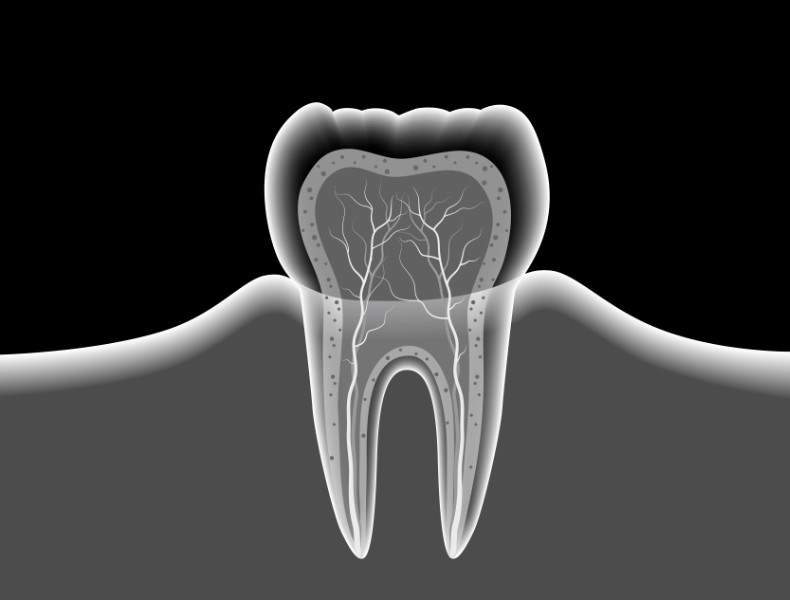

radiografia endorale

La radiografia dentale, o radiografia endorale, mostra l’immagine di singoli denti nelle loro dimensioni reali.

Ogni singola immagine può rappresentare uno o due denti adiacenti.